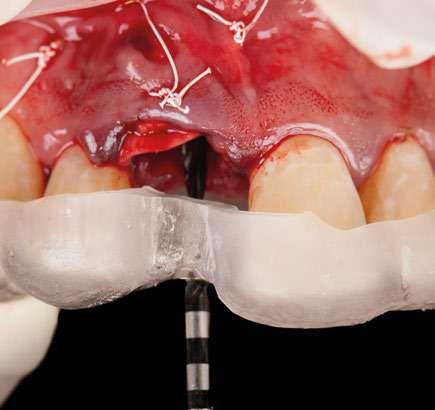

Planificación

Una vez tenemos todos los datos, decidimos como primera opción realizar una cirugía guiada post extracción con regeneración y carga inmediata.

Otra de las ventajas que nos ofrece el software de diagnóstico y planificación DTX StudioTM Implant es la posibilidad de diseñar una férula quirúrgica y exportarla con el fin de poder imprimirla de manera local y acortar así los tiempos de preparación.

A la hora de imprimir nuestra férula localmente, apostamos por utilizar la impresora SprintRay, que de manera muy fácil e intuitiva nos permite imprimir un sinfín de materiales de forma predecible, obteniendo resultados muy precisos y rápidos, es sin duda nuestra impresora de elección por tecnología y materiales.

Aparte de ello, la función TempShellTM nos permite también exportar el diseño de la futura restauración con el fin nuevamente de poder tener un provisional impreso preparado el día de la cirugía. Se trata sin duda de una revolución en cuanto al control de todos nuestros procesos, y en cuanto a eficiencia a la hora de preparar y realizar una cirugía tan compleja.

Cirugía

Con toda nuestra cirugía perfectamente diagnosticada y planificada solo nos queda ejecutarla. 1.- Quitamos la corona ferulizada.

EN IMPLANTOLOGÍA 20 eldentistamoderno mayo/junio 2024

2.- Extraemos de manera meticulosa la raíz del diente afectado.

3.- Legramos toda la zona del lecho implantario con el fin de poder eliminar cualquier resto de tejido de granulación.

4.- Desepitelizamos en margen gingival.

5.- Tunelizamos el defecto vestibular para alojar el injerto de tejido conectivo.

6.- Colocamos injerto de tejido conectivo.

7.- Interponemos membrana reabsorbible entre tejido conectivo y alveolo.

8.- Realizamos osteotomía mediante férula quirúrgica utilizando fresa piloto.

21 eldentistamoderno mayo/junio 2024

9.- Seguimos preparando el lecho utilizando fresado biológico con la OsseoShaperTM

10.- Colocamos implante Nobel Biocare N1TM TiUltra de 3,5x13.

11.- Observamos el torque obtenido de 50N por lo tanto podemos realizar carga inmediata.

12.- Colocamos aditamento N1TM Base XealTM con el fin de trabajar la prótesis a nivel gingivall.

13.- Colocamos pilar provisional.

14.- Rellenamos el gap con creos xenogainTM, compactando para que el hueso llegue lo más apical posible y cubra la superficie implantaria expuesta.

15.- Cortamos pilar provisional y adaptamos el TempShellTM con composite. Podemos comprobar la predictibilidad en cuanto a la posición 3D planificada de nuestro implante.

WORKFLOW

16.- Colocamos restauración provisional atornillada y fuera de oclusión y traccionamos hacia coronal de los tejidos.

17.- Verificamos nuestro tratamiento con CBCT.